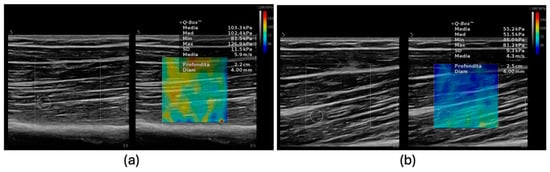

3.5. New Technologies: Shear Wave Elastography and Quantitative Ultrasound

Recently, novel US based techniques have been evaluated as adjunctive tools in the diagnosis of sarcopenia. Preliminary evidence suggests a possible role of shear wave elastography (SWE), a method used to assess tissue stiffness, in the assessment of muscle quantity and quality [] (Figure 4). SWE velocities have shown a significantly lower value in sarcopenic patients and have been positively correlated with grip strength []. These results could be related to the muscle structural rearrangements that occur in sarcopenic patients with increased adipose tissue deposition and fibrosis.

Figure 4.

Differences in muscle stiffness evaluated by SWE. (a) Elevated stiffness in an old patient with myosteatosis and sarcopenia (103.3 kPa). (b) Lower stiffness in a young patient (55.2 kPa). SWE, shear wave elastography, kPa, kilopascal.